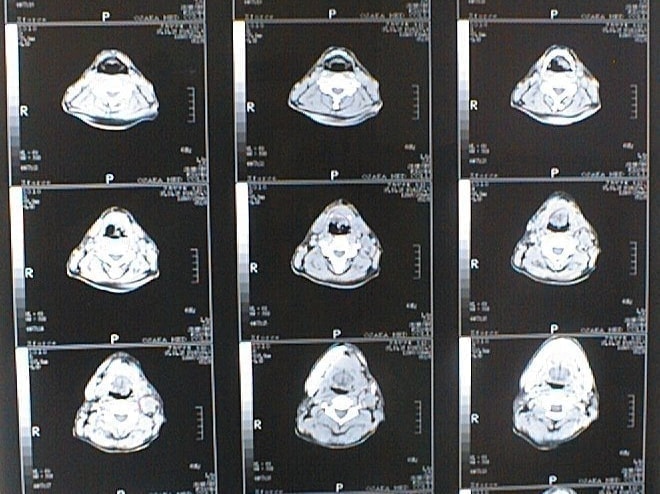

CT画像比較

中咽頭末期がんCT画像①

入院当時CT画像①

中咽頭末期がん消滅CT画像①

入院3か月後癌消滅CT画像①